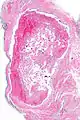

Pathology

Histopathology Images